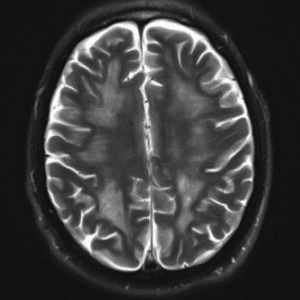

Case #32

Intravascular lymphoma